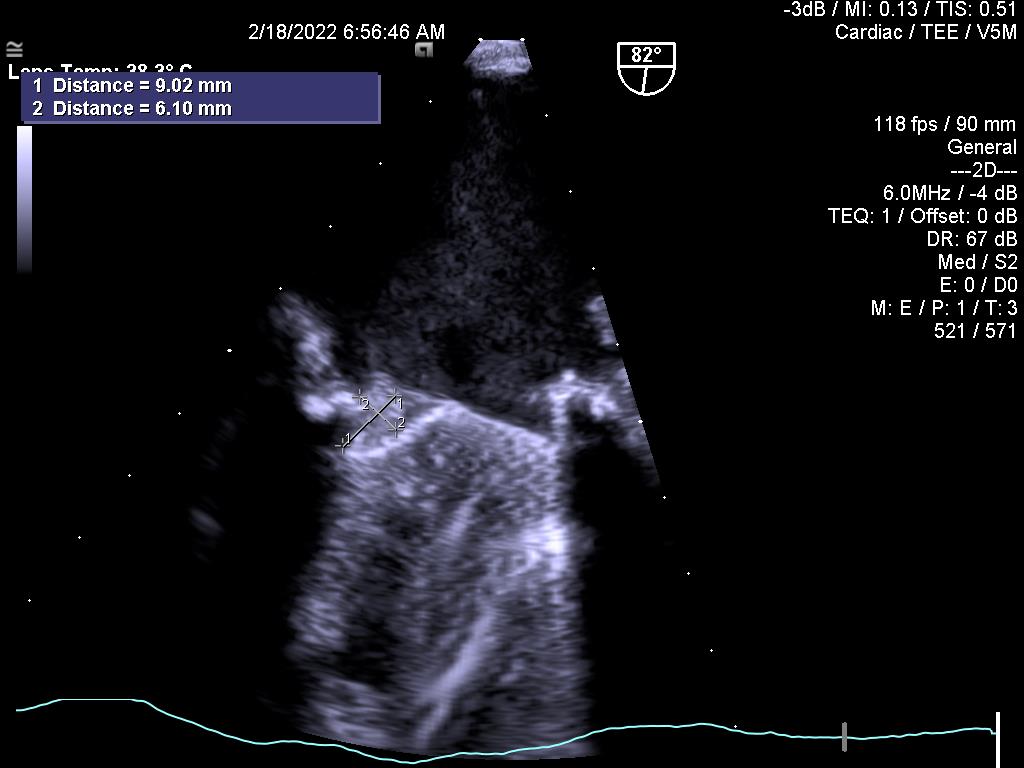

3.Huyết khối tiểu nhĩ trái trên bệnh nhân hẹp van 2 lá (không thấy được trên siêu âm tim qua thành ngực)

4.Sùi nhỏ ở mặt nhĩ ở bệnh nhân hở van hai lá nặng bị viêm nội tâm mạc nhiễm trùng (Bệnh Osler) (siêu âm tim qua thành ngực không thấy sùi)